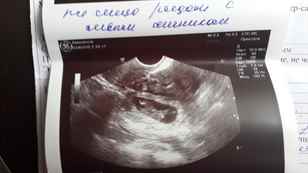

Видны ли признаки внематочной беременности на УЗИ?

УЗИ не всегда является информативным методом, так как на ранних сроках заметить плодное яйцо бывает невозможно и часто могут спутать сгустки крови или слизи в матке с маточной беременностью. Случалось наблюдать, что у женщины одновременно развивается две беременности, одна из которых маточная, которую и видит аппарат УЗИ, другая – внематочная. Если все же УЗИ тоже не подтверждает внематочную беременность, а подозрения на нее есть, то женщину могут положить в больницу для проведения соответствующей диагностики и лечения.